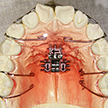

6. 上顎歯列拡大装置

セファロ計測や診断用模型等により、上顎は現段階での劣成長を認めるため、時期が遅いとは思いましたが上顎歯列の拡大目的で(少しでも上下歯列関係は好転したかった)、術前処置として装置にて行いました。